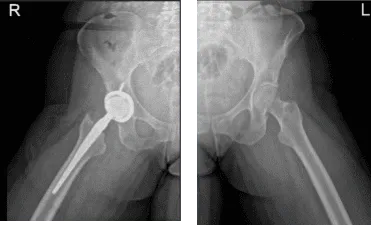

A la paciente se le dio el estado tras la artroplastia total de cadera derecha usando Zimmer, dijo que durmió de lado «por error» y que sintió la cadera dislocada. Presentó una radiografía que mostró una artroplastia total de cadera derecha, en buena alineación. No hay fracturas.

Cadera bilateral con pelvis 3 o 4 más vista